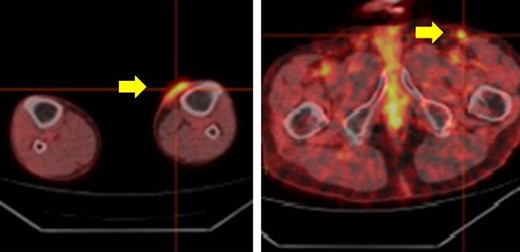

The whole body PET-CT (yellow arrow indicates accumulation of FDG).